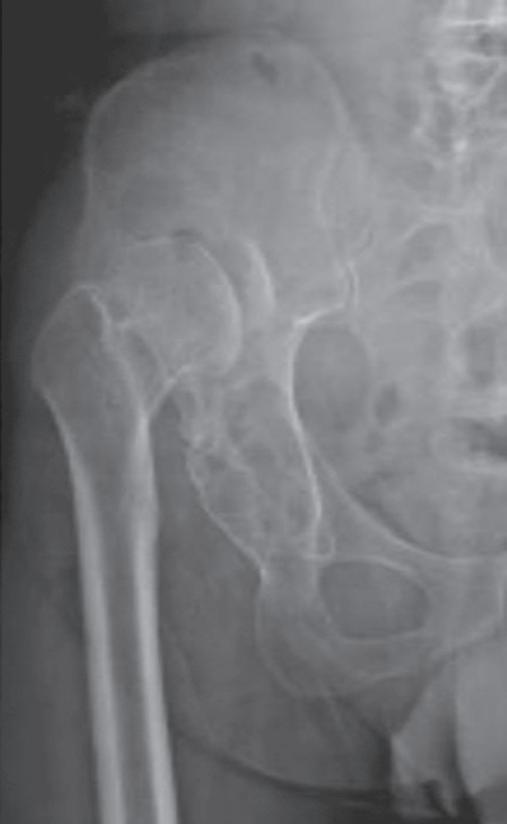

Com uma incidência de 2 a 4%, os distúrbios da maturação do quadril estão entre as malformações mais comuns do sistema musculoesquelético. A displasia do quadril é a causa mais comum de coxartrose precoce em todo o mundo, com a consequência da artroplastia precoce do quadril na idade do jovem adulto [18]. Para os afetados, a doença geralmente está associada a muito sofrimento ( ▶ Fig. 1.3).

Fig. 1.3 Consequências tardias de uma luxação do quadril.

a Coxa vara após necrose da cabeça femoral.

b Artrose na displasia do teto acetabular.

c Luxação inveterada do quadril.